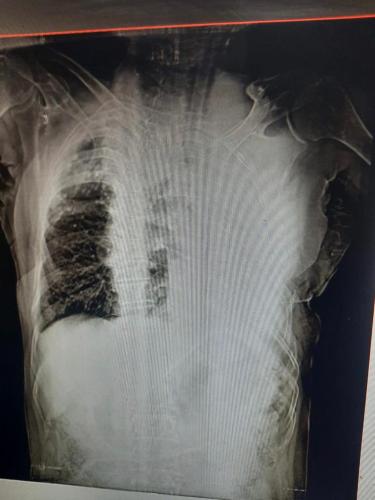

Photo Gallery Dr. Monika Gupta - Photo Gallery 7 5 2 8 6 Dr. Atul Kumar Gupta - Photo Gallery « ‹ of 3 › » Video Gallery